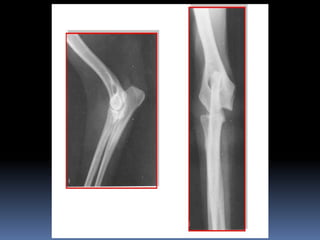

Juana, la iguana

Sam, el costurero